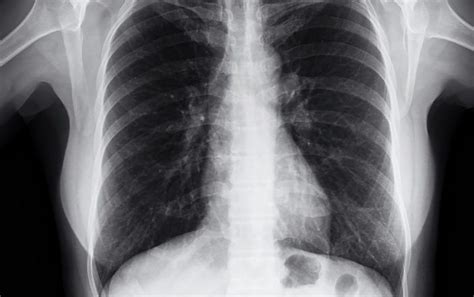

Medical imaging is where incidental findings are commonly discovered. Think MRIs, CT scans, ultrasounds, and X-rays. These scans are amazing at providing detailed images of our insides, but they can also pick up on things that weren’t the initial focus. For instance, when doctors use CT scans to look for lung problems, they might also stumble upon a nodule in the liver. It’s like a bonus finding! This is why radiologists play a crucial role. They are trained to spot these types of findings and inform the referring physician. However, the use of advanced imaging techniques is increasing, as is the likelihood of detecting these incidental findings. This, therefore, puts more pressure on healthcare providers to have a systematic approach to managing these. Imaging techniques aren’t perfect, and the detection of incidental findings comes with its own set of challenges and risks. One of the main concerns is the potential for false positives . This is where an image appears to show a problem when, in reality, it’s not present. False positives can lead to unnecessary anxiety, additional testing, and even invasive procedures, which are all associated with increased healthcare costs and patient discomfort. Conversely, there is a risk of false negatives , where an incidental finding is missed altogether. This is particularly problematic if the finding represents a serious health condition. The accuracy of imaging also depends heavily on the quality of the equipment and the expertise of the radiologist. High-resolution equipment and experienced radiologists are better at both detecting and interpreting incidental findings accurately. Due to these complexities, it is important to weigh the risks and benefits of imaging against each patient’s individual situation and medical history. Decisions on imaging should not be made lightly, and it’s essential to communicate clearly with the patient about the potential for incidental findings and their implications.